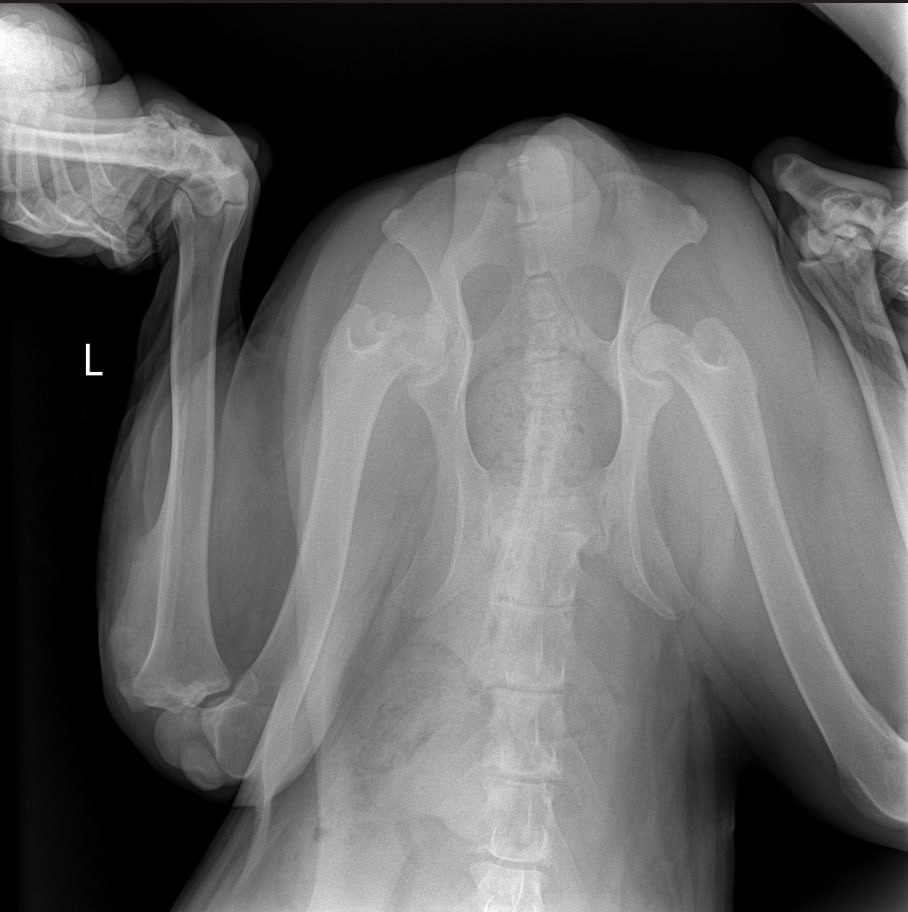

Рентген

Описание рентгена

Интересно, а изменения в бронхах на рентгене от диро или результат хронического бронхита?

Сильнейший коксартроз тбс на больной лапе.....который не заметили на первичных осмотрах....зато настаивали в необходимости кастрации. В результате изменения положения лапы, нагрузки - воспаление и боль.